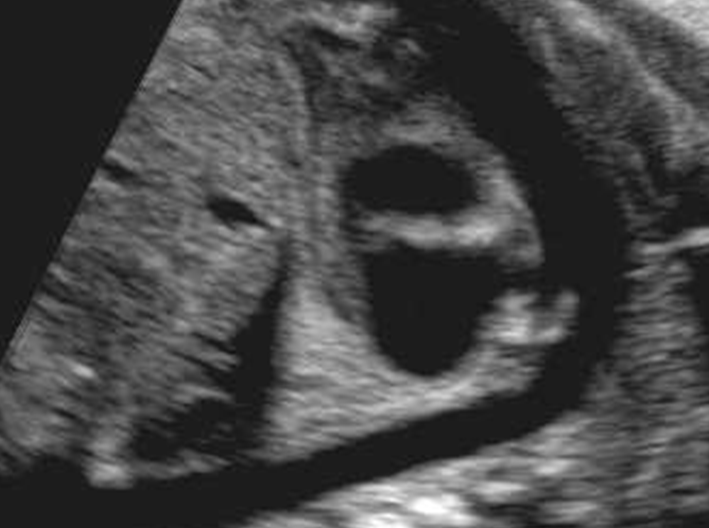

4 chamber view

Normal 4 chamber view

Identify structures of the heart